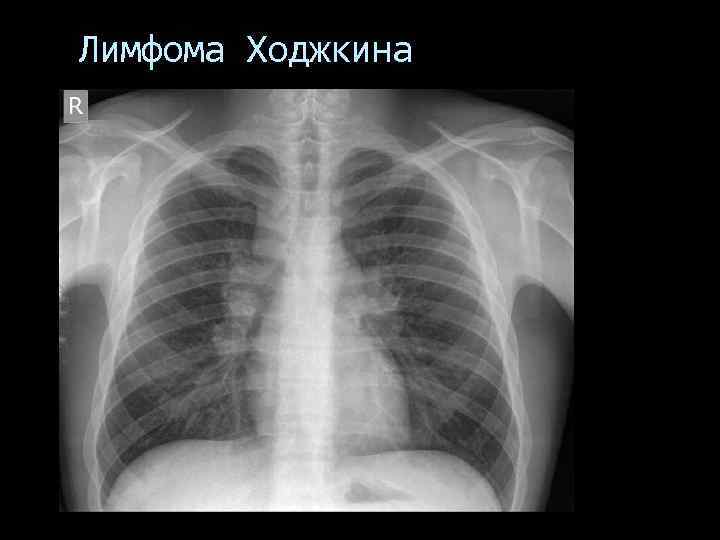

Лимфома Ходжкина В переднем сегменте правого легкого неправильной формы участок инфильтративного уплотнения легочной ткани с нечеткими наружными контурами, медиальной частью он сливается с тенью средостения. По периферии инфильтрата видны полостные образования до 1, 0 1, 5 см диаметром с четкими внутренними контурами. Прилежащие отделы висцеральной плевры по ходу малой междолевой щели утолщены.

Лимфома Ходжкина